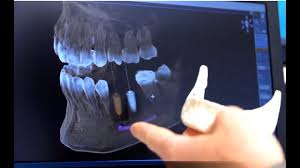

Röntgen beim zahnarzt wie oft im jahr. Dabei unterstützen uns auch zahlreiche Technologien wie beispielsweise das elektronische Längenmessgerät das uns während der Wurzelkanalbehandlung mitteilt wo der Wurzelkanal endet ohne dass hierfür eine Röntgenaufnahme notwendig wird. Die Anwendung von Röntgen erfolgt nach dem strengen Grundsatz. Das gilt etwa bei erhöhtem Kariesrisiko oder wurzelbehandelten Zähnen Zahnärzte müssen jedes Mal über die Notwendigkeit des Röntgens aufklären.

So wenig wie möglich so viel wie nötig. Mein Sohn 10 J ist in kieferorth. H äufiges Röntgen der Zähne erhöht das Risiko für einen gutartigen Hirntumor.

News Medizin Röntgen beim Zahnarzt als Meningeomrisiko. Ihr SSO-Zahnarzt hat diese Abwägungen in vielen Ausbildungs-stunden gelernt und wird sich entsprechend verantwortungsvoll verhalten. Röntgen sehr schädlich wie oft.